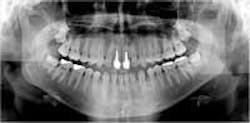

CCD-based intraoral and extra-oral digital X-ray systems can produce striking, high-resolution, diagnostic-quality digital images that rival, and in some instances, even exceed film in diagnostic quality. These solid-state-based digital radiograph systems are rapidly becoming the way of the future in the dental profession, and will no doubt soon be the adopted standard of care in our profession. (See Figures 1 and 2.)